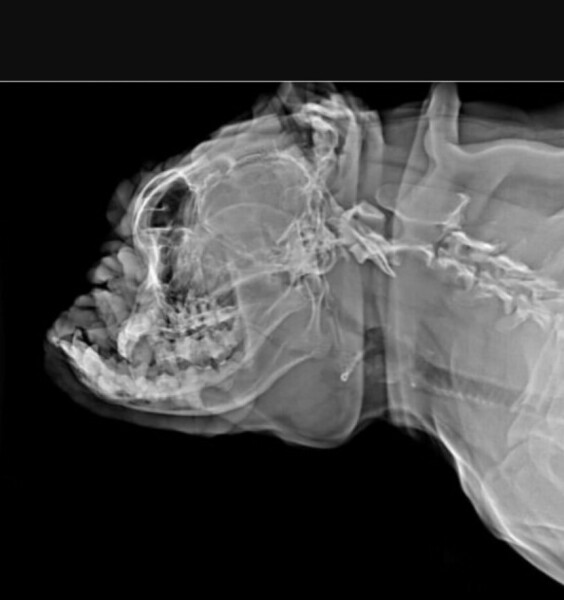

This looks comfortable doesn't it?

As I was looking up my references on CKC percentages, I came across these comparison photos I had saved. (Credit: I almost certainly got these from Jemima Harrison on Twitter - for this interested in seeing regular comparisons on how some breeds used to be much healthier when less extreme).

One of a Frenchie in the ring. One of a Frenchie, bred in Canada by a breeder attempting to moderate the extremes of the breed to produce a much healthier dog.

The healthier dog is, by far, also the better looking dog, imo, and yet it would fail in the show ring.